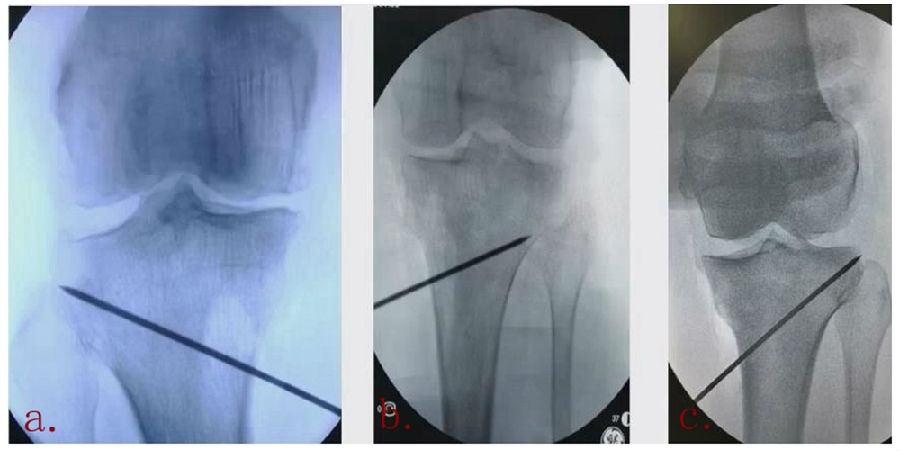

1、综合判断力线的方法

现在对于力线的判断大致通过以下几方面:①大体形态;②透视确定力线,连接股骨头中心、踝关节中心,看力线杆和膝关节中心的位置关系;③MPTA(胫骨平台关节线和胫骨侧机械轴夹角);④PSI。

1、原因及预防

(1)肢体外旋

一般来说在麻醉状态下肢体会处于外旋位,此时去测定力线的话往往需要将肢体放在旋转中立位,但是在内旋肢体的过程中会出现内翻应力,那么这种情况下判断力线会带来误差,所以通常建议大家要把手术床做一点旋转,让患肢处于自然的旋转中立位,这样再去判断力线就比较准确。

(2)MCL浅层未彻底松解

对于MCL,大多数忽视的是后侧束,如果不能把后侧束彻底松解,那么在撑开过程中往往会感觉撑不开,此时如果过度去撑开的话,会导致在关节内侧出现很大的压力,所以这时对力线会产生一定的误导。

(3)力线验证未模仿负重应力

现在所谓的目标力线应该是模仿负重时的力线。做截骨时,通常会将力线轻度外移,如果没有考虑关节内畸形、韧带松弛或是软骨磨损,那么在负重时,在内侧副韧带撑开过程中,会出现力线偏移。所以要注意,手术中间在调整目标力线时,要以应力状态下为标准。

(4)拉力螺钉加压过度

拉力螺钉的过度使用可能会引起矫形位置的角度丢失。当拉力过度时,会将力线由内侧向外侧轻度拉回,使力线丢失一部分,所以切忌过度使用。